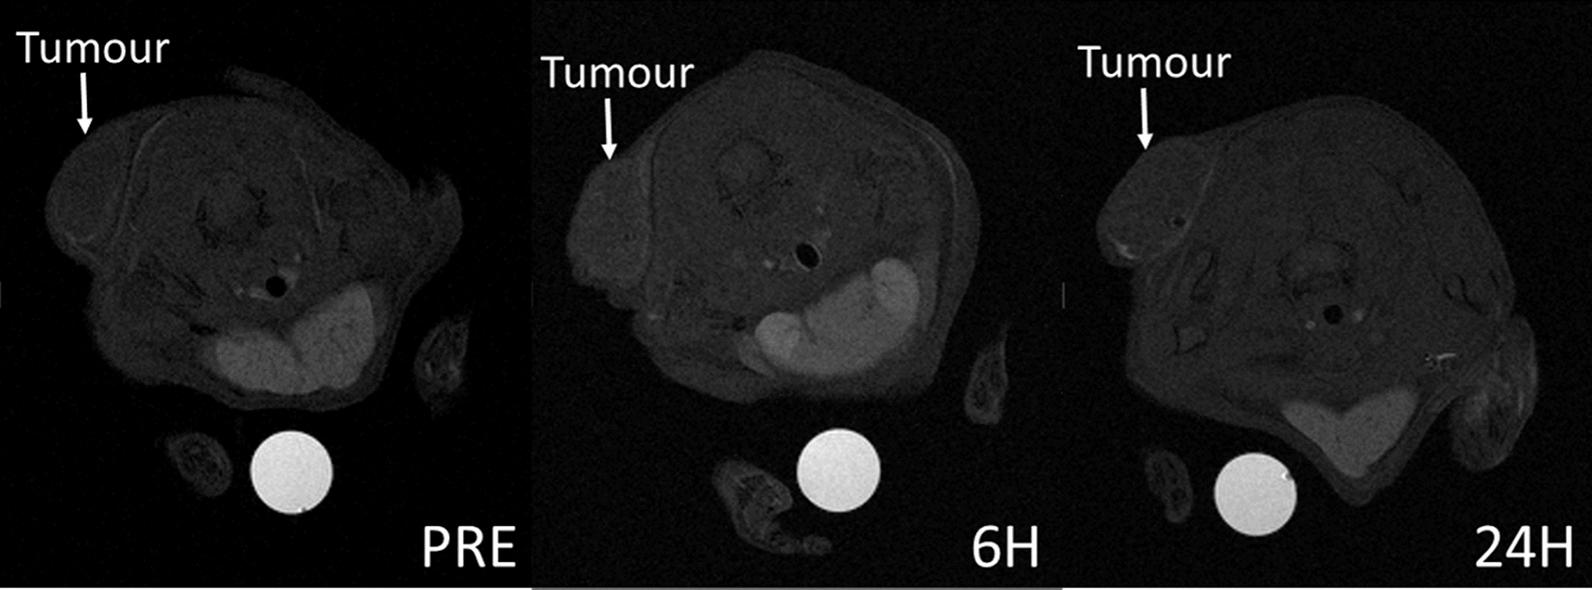

PTX and Gd-AAZTA-C17 loaded LDLs (LDL-PTX-Gd) have been prepared, characterized and their stability was assessed under 72 h incubation at 37 °C and compared to LDL loaded with Gd-AAZTA-C17 (LDL-Gd) and LDL-PTX. The cytotoxic effect of LDL-PTX-Gd was evaluated by MTT assay. The anti-tumour drug loaded into LDLs showed a significantly higher toxicity on B16-F10 cells with respect to the commercially available formulation Paclitaxel kabi (PTX Kabi) used in clinical applications. Tumour cells uptake was initially assessed by ICP-MS and MRI on B16-F10 cell line. By the analysis of the image signal intensity, it was possible to extrapolate the amount of internalized PTX indirectly by the decrease of relaxation times caused by Gd, proportional to its concentration. Finally, the treatment with PTX loaded LDL on B16-F10 tumour bearing mice resulted in a marked reduction of tumour growth compared to the administration of PTX Kabi alone.

已经制备、表征了负载 PTX 和 Gd-AAZTA-C17 的 LDL(LDL-PTX-Gd),并在 37°C 下孵育 72 小时后评估其稳定性,并与负载 Gd-AAZTA-C17 的 LDL(LDL-Gd)和 LDL-PTX 进行比较。通过 MTT 测定评估 LDL-PTX-Gd 的细胞毒性。与临床应用中使用的市售制剂紫杉醇卡比(PTX Kabi)相比,负载于 LDL 中的抗肿瘤药物对 B16-F10 细胞表现出显著更高的毒性。通过 ICP-MS 和 MRI 最初评估肿瘤细胞摄取。通过分析图像信号强度,可以通过 Gd 引起的弛豫时间的降低间接推断出内部化的 PTX 的量,这与 Gd 的浓度成正比。最后,与单独给予 PTX Kabi 相比,用负载 PTX 的 LDL 治疗 B16-F10 荷瘤小鼠导致肿瘤生长明显减少。